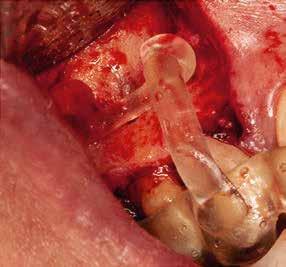

a-m. ábrák: Preoperatív röntgenfelvétel (a) és preoperatív CBCT-felvétel a jobb felső 5-ös (1.5) fogról, sagittalis (b) és axialis (c) nézetek. Az intraorális szkennelés során kapott STL-fájl (d). A 1.5-ös fog navigált endodonciai mikrosebészeti beavatkozásához tervezett sablon (e). A 1.5-ös fog navigált endodonciai mikrosebészeti beavatkozásához nyomtatott sablon (f). Teljes vastagságú mucoperiostealis lebenyt emeltünk (g). A sablont a helyére illesztettük, és a csontablak határait jelöltük (h). A fog gyökerén kívül eső, betört eszköz a 1.5-ös fog periapicalis régiójában (i). Az eltávolított betört eszköz (j). A rezekció, retrográd preparáció és a TotalFill BC RRM Fast Set Putty anyaggal elkészített retrográd gyökértömés utáni röntgenfelvétel (k). A lebenyt varratokkal rögzítettük (l). A kétéves kontroll során készített röntgenfelvétel (m).

gítségével tovább módosítottuk. Az így kapott sebészi sablon egyértelműen meghatározta a periapikális terület eléréséhez szükséges csontablak határait (2. e-f. ábra) Helyi érzéstelenítést követően teljes vastagságú mucoperiostealis lebenyt képeztünk, majd a buccalis csont feltárását követően (2. g. ábra) a sablon segítségével bejelöltük a preparálandó csontablak határait (2. h. ábra). A csontablak kialakítása során Piezotome CUBE LED kézi-darabot alkalmaztunk, majd a leemelését követően a betört eszközt megkerestük (2. i. ábra) és eltávolítottuk (2. j. ábra). A rezekciót ultrahangos megmunkáló fejekkel (ACTEON) végeztük, majd retrográd preparáció következett.

A retrográd gyökértömés elkészítése során TotalFill BC RRM Fast Set Putty-t (FKG) használtunk (2. k. ábra). A lebeny széleit 5/0-s Prolene varratokkal egyesítettük (2. l. ábra). A varratok a műtétet követően 72 órával kerültek eltávolításra. A beteg két évvel később kontrollröntgen készítése céljából érkezett rendelőnkbe. A vizsgálat során a fog tünetmentesnek és funkcióképesnek bizonyult (2. m. ábra).

Egy 38 éves nőbeteg a korábban kezelt jobb felső második kisőrlőfogából (1.5) kiinduló mérsékelt fájdalom miatt jelentkezett rendelésünkön. A kórtörténetében jelen panasza szempontjából releváns információ nem szerepelt. A beteg a klinikai vizsgálat során vertikális kopogtatásra enyhe érzékenységet jelzett. A kérdéses fog körül mérhető szondázási mélység és a fogmobilitás fiziológiás volt. Periapicalis röntgenfelvételen egy, a fog gyökércsúcsán túl presszálódott betört gyökérkezelő műszerből származó eszközfragmentumot láttunk (2. a. ábra). A preoperatív CBCT-felvétel a buccalis csontlemez épségét igazolta (2. b-c. ábra). A fog revíziója öt hónappal korábban történt. A már előzőleg gyökérkezelt, gyökértömött, majd revideált 1.5-ös fog esetében a diagnózisunk periodontitis periapicalis symptomatica volt. A periapikális elváltozás kezelése érdekében navigált endodonciai mikrosebészeti beavatkozást végeztünk.

A felső állcsontról intraorális szkent (TRIOS) készítettünk, és az ezáltal kapott STL fájlt (2. d. ábra) a CBCT-felvétel során nyert DICOM fájlokkal a Zirkonzahn.Implant-Planner (Zirkonzahn) szoftverben egyesítettük. A sebészi sablont ebben a programban megterveztük, majd a Meshmixer (Autodesk) szoftver se-